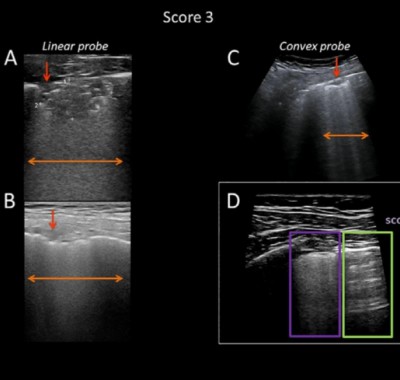

L’ecografia polmonare è una tecnica diagnostica utile a valutare malattie del polmone e della membrana che lo avvolge (pleura), nonché ad ottenere informazioni sulla presenza di versamento pleurico e pneumotorace, cioè un accumulo anomalo di aria nello spazio fra polmoni e parete toracica. In alcuni casi l’ecografia polmonare è preferibile alla radiografia per evitare l’esposizione ai raggi X.Per ottenere l’immagine del polmone si utilizza una sonda ecografica che invia ultrasuoni all’organo e converte in segnali elettrici le onde sonore che riceve di ritorno. Un computer analizza e trasforma questi segnali in immagini.

Sebbene sia utile nella diagnosi e nel monitoraggio di diverse patologie respiratorie, l’ecografia polmonare presenta diversi limiti. Se fra la lesione da osservare e la sonda si frappone anche una minima porzione di polmone normalmente areato, gli strati più profondi dell’organo non risultano visibili. L’ecografia polmonare è quindi utile a individuare patologie che provocano un aumento della densità del polmone, ma non è in grado di valutare la quantità d’aria presente nell’organo (ventilazione). Tali limiti sono superabili integrando l’ecografia con i dati clinici.